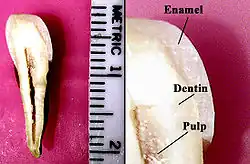

Tooth enamel is one of the four major tissues that make up the tooth in humans and many animals, including some species of fish. It makes up the normally visible part of the tooth, covering the crown. The other major tissues are dentin, cementum, and dental pulp. It is a very hard, white to off-white, highly mineralised substance that acts as a barrier to protect the tooth but can become susceptible to degradation, especially by acids from food and drink. In rare circumstances enamel fails to form, leaving the underlying dentin exposed on the surface.[1]

Enamel is the hardest substance in the human body and contains the highest percentage of minerals (at 96%),[2] with water and organic material composing the rest.[3] The primary mineral is hydroxyapatite, which is a crystalline calcium phosphate.[4] Enamel is formed on the tooth while the tooth develops within the jaw bone before it erupts into the mouth. Once fully formed, enamel does not contain blood vessels or nerves, and is not made of cells. Remineralisation of teeth can repair damage to the tooth to a certain degree but damage beyond that cannot be repaired by the body. The maintenance and repair of human tooth enamel is one of the primary concerns of dentistry.

The large amount of mineral in enamel accounts not only for its strength but also for its brittleness.[6] Tooth enamel ranks 5 on Mohs hardness scale (between steel and titanium) and has a Young's modulus of 83 GPa.[4] Dentin, less mineralized and less brittle, 3–4 in hardness, compensates for enamel and is necessary as a support.[7] On radiographs, the differences in the mineralization of different portions of the tooth and surrounding periodontium can be noted; enamel appears lighter than dentin or pulp since it is denser than both and more radiopaque.[8]

The basic unit of enamel is called an enamel rod.[7] Measuring 4–8 μm in diameter, an enamel rod, formally called an enamel prism, is a tightly packed mass of hydroxyapatite crystallites in an organized pattern.[2] In cross section, it is best compared to a keyhole, with the top, or head, oriented toward the crown of the tooth, and the bottom, or tail, oriented toward the root of the tooth.